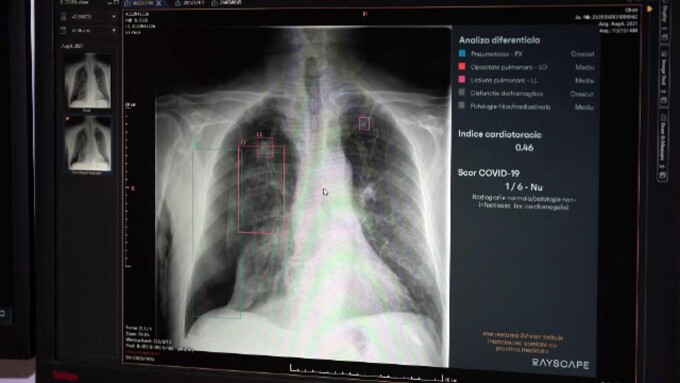

La Spitalul Județean din Timișoara, medicii radiologi folosesc de 5 ani o astfel de aplicație pentru diagnosticarea afecţiunilor pulmonare.

Marius Benţa, medic specialist SJU Timişoara: „Într-un volum mare de muncă, poate să apară oboseala, în special în gărzile de noapte. Ne vin în ajutor aceste aplicații care ne evidențiază leziunile.”

Sistemul, dezvoltat de un start-up din Timișoara, este utilizat și peste hotare.

Bogdan Bercean, cofondator start-up: „Învață patternurile, tiparele de gândire ale radiologilor, nu identifică în locul medicilor. Colaborează cu medicul radiolog.”